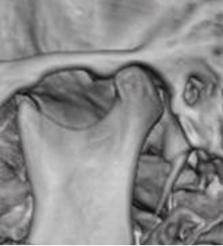

Fig 3B. ATM normal.

TAC en reconstrucción 3D.